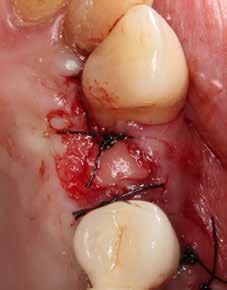

A foggyökér óvatos, atraumatikus eltávolítását követően excochleáltuk a parodontális és periapikális gyulladásos folyamatok eredményeként jelen lévő sarjszövetet. Az alapos tisztítás és a bukkális csontfal hiánya miatt indokolt membrántechnika megfelelő kivitelezése céljából mukoperioszteális lebenyt képeztünk, a lebeny tervezésénél arra törekedtünk, hogy az a lehető legkisebb méretű legyen és a második kisőrlő fog helyén lévő implantátum hámtapadását ne érintse, illetve, hogy lehetővé tegye a szemfog parodontális kezelését is (3., 4. ábra). Az alveoláris csont megőrzésének és regenerációjának segítése céljából a fog eltávolításával egy időben alveólus prezervációt végeztünk Stikcy Bone™ és PRF membránok segítségével, melyek előállításánál követtük a J. Choukroun által megadott vérvételi és centrifugálási protokollt (20). Kizárólag Process for PRF Duo Quattro System eszközöket, centrifugát, vérvételi egységet és csöveket, a membránok előállításához PRF Box-ot használtunk. Az A-PRF és S-PRF csöveket a PomPac eljárásnak megfelelően 4 °C-ra előhűtöttük. A Stikcy Bone™ készítmény előállításához Purgo™ xenografot használtunk. Az alveolust a grafttal feltöltöttük, tömörítő műszerrel enyhe kompreszsziót, illetve vertikális irányban 10 százaléknyi túlkompen-

zációt alkalmaztunk  (5., 6. ábra). Ezt követően a palatinális marginális gingivát óvatosan alápreparálva a bukkális defektust, valamint az okkluzális felszínt keresztirányban

A-PRF membránokkal borítottuk (7. ábra). A mukogingivális lebenyt – annak megnyújtása nélkül – a helyére fektettük és varratokkal rögzítettük, per primam sebzárást nem végeztünk (8., 9. ábra). A varratokat 2 hét után távolítottuk el, a varratszedésig a sebgyógyulás támogatására per os 1000 mg/nap C- és 12 000 NE/nap D-vitamint adtunk (20). A műtéti beavatkozást 24 hét gyógyulási időszak követte, melynek során sem helyi, sem gyógyszeres kezelés nem történt, az esztétikum javítása érdekében a páciens ideiglenes kivehető fogpótlást használt. A csontos gyógyulás ellenőrzése és az implantáció tervezése céljából állcsonti CT felvételt készítettünk, illetve lenyomatvételt végeztünk. A CT felvételen tökéletes csontos gyógyulást észleltünk, az alveolaris csont volumene teljes mértékben megtartott volt (10. ábra), a klinikai kép is ennek megfelelően alakult (11., 12. ábra)